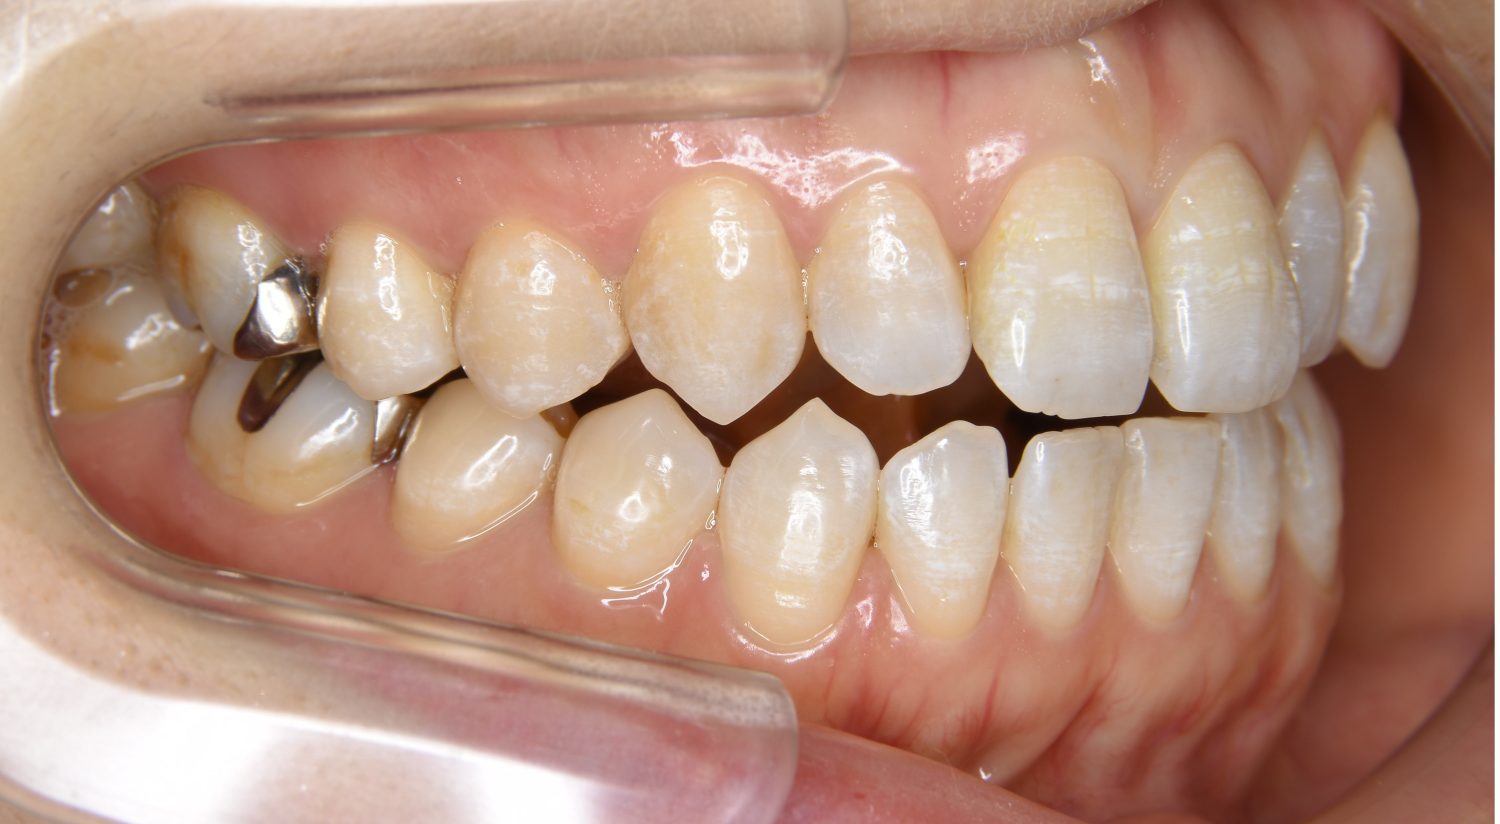

叢生の症例紹介②

Before

主訴

歯の凸凹を治したい。

治療内容

アライナー(インビザライン)にて非抜歯で治療を行いました。

治療費

1,150,000 円(税込)

治療期間

26ヶ月

通院回数

14回

想定されたリスク

※歯根吸収、歯肉退縮、歯髄壊死、顎関節症状

※アライナー(インビザライン)は日本の薬機法未承認の矯正装置であり、医薬品副作用被害救済制度の対象外となる場合があります。

上下前歯部に叢生(凸凹)が認められる状態でした。歯列の遠心移動を行うことで機能面および審美面が改善されました。